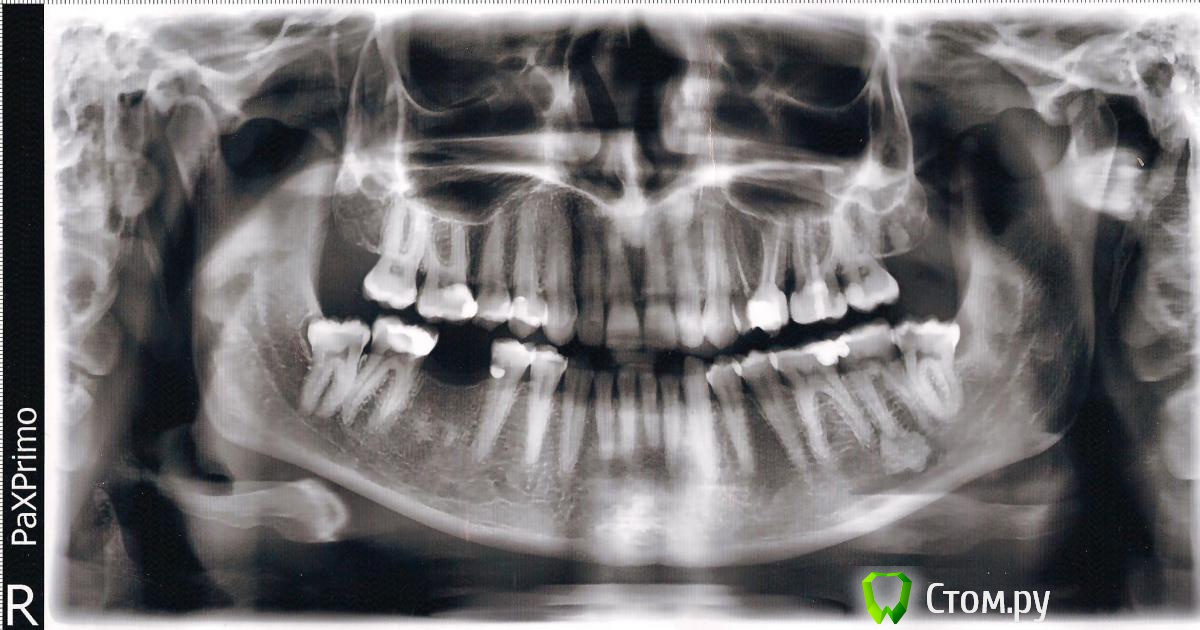

Ольга* Опубликовано 3 апреля, 2014 Поделиться Опубликовано 3 апреля, 2014 (изменено) Здравствуйте. Две недели назад мне удалили зуб мудрости (левую нижнюю восмёрку). После удаления у меня были сильные боли, очень долго лунка не заживала. Ходила к врачу, он говорил, что было сложное удаление и так должно быть. Сейчас боли немного утихли, но всё равно лунка беспокоит. Чтобы убедится,что всё нормально, я сходила сделал рентген. На рентгене в лунке какое-то белое пятно, Скажите пожалуйста в каком сотояянии лунка и что это за пятно. Изменено 3 апреля, 2014 пользователем Ольга* Ссылка на комментарий

Ольга* Опубликовано 3 апреля, 2014 Автор Поделиться Опубликовано 3 апреля, 2014 может быть с содержанием йода, или еще какого антисептика, а снимка до удаления у вас нет?Да йод скорее всего. Я до сих пор его чувствую, не знаю должно так быть или нет, прошло уже 2 недели. Вот снимок до лечения. Ссылка на комментарий